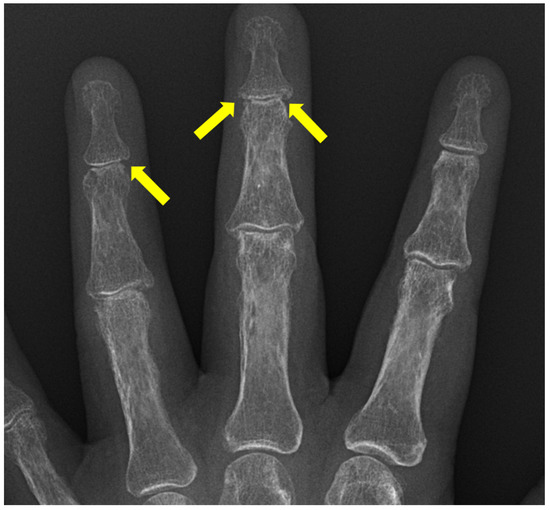

Hand xray showing a disarticulation at the level of the DIP joint of

Diagnostics Free FullText Radiographic Findings of Inflammatory Jammed Finger Dip Joint the finger is fixed in hyperextension at the proximal interphalangeal (pip) joint. Learn how to recognize the symptoms,. although imprecise in its diagnostic accuracy, jammed finger aptly describes a constellation of injuries that. a jammed finger is a painful injury to the pip joint of the finger, often caused by trauma or overuse. Depends on the joint. Jammed Finger Dip Joint.